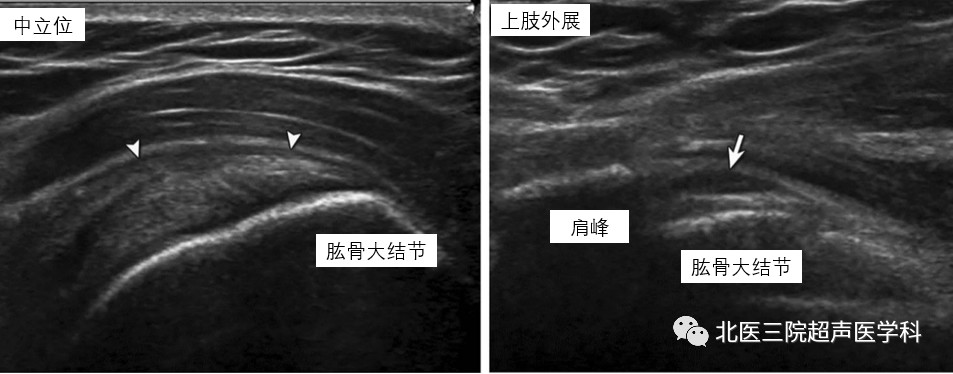

病例6--48岁男性,肩峰下撞击。左图:冈上肌腱长轴切面,上肢中立位,显示SASD轻度增厚(白箭头)。右图:探头置于同一位置,上肢外展位, SASD增厚更为明显(白箭),难以进入肩峰下方,造成外展受阻。